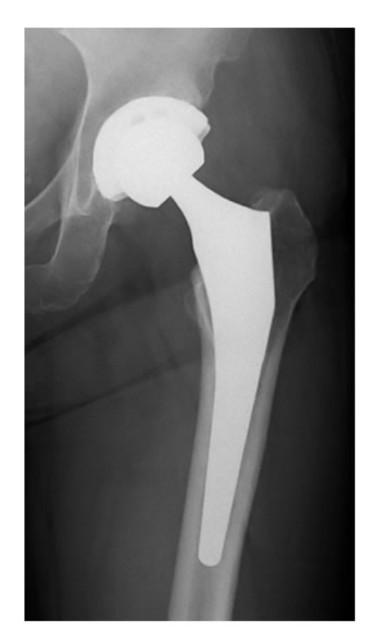

昨日はグロッキー!熱も出るし、体調悪!このまま熱発で死ぬんとちゃうか?ダサ! やはり骨盤に及ぶ4hのOpeは応えたんでしょうね。今日はもう大丈夫です。と、嬉しかったこと、REBEL500を買ったとバイク屋の元大将にゆーと、えーのこーたやん!どこが?無理せんでも乗れるポジション、自分はまだ無理なポジション無理やろ?そのとーり。僕の選択は正しかった。

f:id:SAKI001:20250601074434j:image